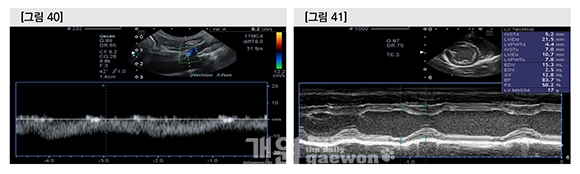

Portal vein의 flow velocity는 8.2cm /sec 로서 문맥을 통한 간의 blood supply는 양호하였다. 심장초음파상에 이완기말 좌심실 직경(LVDd)이 21.5mm로서 참고범위(13.97~16.24mm) 이상 이었으며, LA/Ao 1.89로서 volume overload에 대한 remodeling은 변화가 없었다.